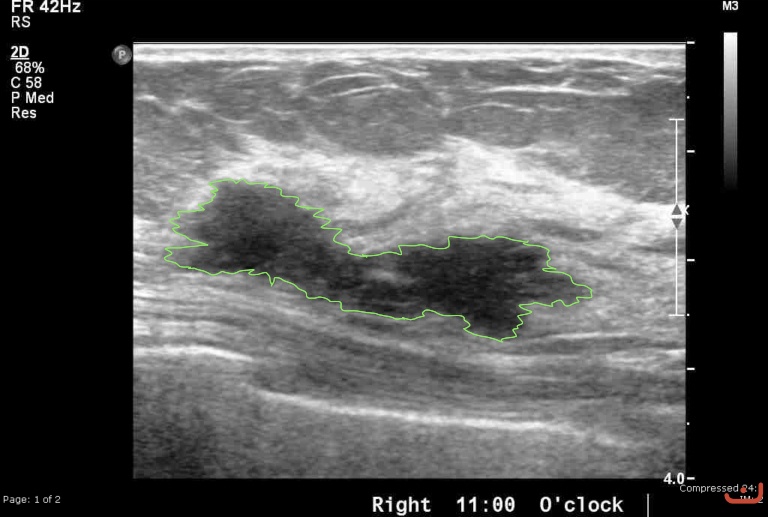

Case 21-G1

Malignant solid mass

Friday, 22 May 2015

186.89 KB (768 x 517 px)